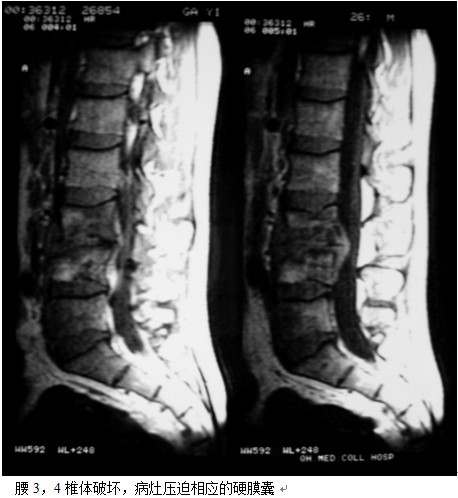

本组46例中男28 例,女18 例。年龄17~67岁,病程6 个月~7年,平均11.3 个月。本组患者均为 L1~S1腰段结核。病灶累及2 个椎体31例(L1-2 6例, L2-3 8例,L3-4 10例,L4-5 5例,L5-S1 2例),3 个或3 个以上椎体15例。合并腰大肌脓肿23列,所有患者均有腰背部疼痛,活动受限,双下肢感觉麻木19例,会阴部感觉减退12例,双下肢肌力减弱12例,腱反射减弱12例,术前后凸角(Cobb 角) <30°者12例, 30°~60°者28 例, >60°者6 例,Cobb角平均32.3°4例患者是二次手术。术前均行X线片、CT或者MRI检查。术后病理检查确诊为脊柱结核。

脊柱结核手术治疗的传统术式是病灶清除椎管减压术。其目的是清除病灶及椎管内脓汁、干酪样坏死物、死骨,保障抗痨药物的渗透,促进病灶愈合,解除脊髓压迫。不足之处在于死骨不能完全清除的可能,残留椎间盘不能完全清除的可能。凿开病灶清理后椎体间残留空间大,前中柱结构的破坏和缺失,造成脊柱不稳,后凸畸形加重的可能,造成迟发型神经损伤的可能且植骨块在压力状态下再度脱落吸收的可能性较大。在结核病灶内使用内置物的安全性已经得到实验及临床研究的证实[9、11],内固定的应用使脊柱结核的手术治疗取得了很大进步,但在手术方式的选择上,选择前路病灶清除植骨内固定,还是一期后路经椎弓根内固定结合前路病灶清除植骨融合,目前仍有争议[12、13、14、15、16、17、18、19、20、21],选择前者的学者认为通过一个入路,一次完成所有手术操作,可以避免再行后路内固定的手术创伤,而且椎间植骨的融合率较后外侧融合率高,但前路暴露创伤大,内固定的植入存在一定的风险和困难,前路内固定主要重建脊柱的前中柱,前路内固定适于1-2椎体的的破坏,对于多个椎体的结核前路的手术效果较后路差。选择后者的学者认为,后路固定可以避免在病灶内应用内固定,安全性更有保障,但需要两个切口,创伤大,术中需改变体位,而我们的方法取其两者的优点,只有后侧单一切口,创伤相对小,置入椎弓钉相对容易,而且后路椎弓根钉棒系统固定为三柱固定,作用强大,在清除病灶时,我们选择有脓肿,破坏严重,神经症状重的一侧,通过关节突关节,采用刮,凿,切,咬等方法逐步彻底清除病灶,用椎体撑开器逐步撑开椎间,这样更有利于后凸畸形的矫正。对于前方病灶对硬膜压迫较重的患者,只能先行前路病灶清除,撑开时不必担心前路病灶对的压迫病灶完全清除后,准备植骨床,前路植骨后,可对植骨块用椎弓根系统加压,使其更为稳定。另一侧椎板和关节突处可植入碎骨,融合率明显提高,对于脓肿我们首先充分引流,然后用长的刮勺刮除脓肿壁的脓胎,再用干纱布反复擦拭,只到有大量的出血点,再反复用异烟肼与盐水的混合液加压冲洗创面,可以降低局部的细菌量,最后经皮在病灶中放置硬膜外管,术后注射异烟肼,可以提高局部化疗药物的浓度,减轻毒副反应,对于降低病变的复发也有很大作用。